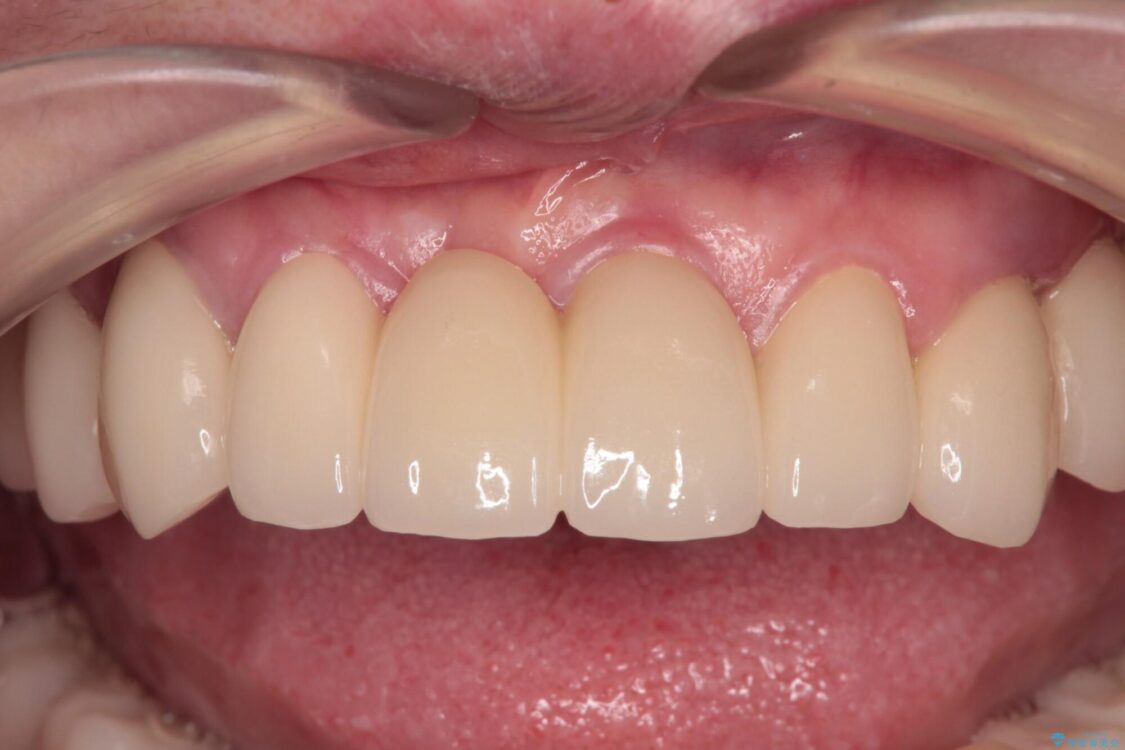

治療後

• 放置したインプラントとインビザライン 全顎リカバリー治療 治療後画像